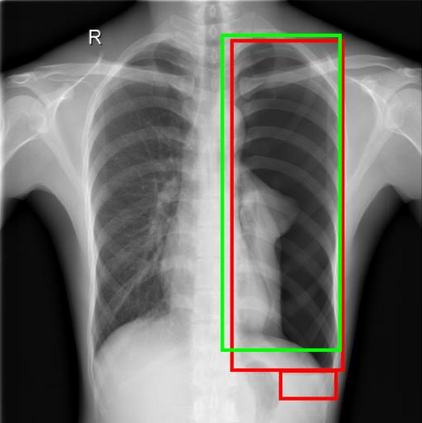

Chest X-ray (CXR) is the most typical diagnostic X-ray examination for screening various thoracic diseases. Automatically localizing lesions from CXR is promising for alleviating radiologists' reading burden. However, CXR datasets are often with massive image-level annotations and scarce lesion-level annotations, and more often, without annotations. Thus far, unifying different supervision granularities to develop thoracic disease detection algorithms has not been comprehensively addressed. In this paper, we present OXnet, the first deep omni-supervised thoracic disease detection network to our best knowledge that uses as much available supervision as possible for CXR diagnosis. We first introduce supervised learning via a one-stage detection model. Then, we inject a global classification head to the detection model and propose dual attention alignment to guide the global gradient to the local detection branch, which enables learning lesion detection from image-level annotations. We also impose intra-class compactness and inter-class separability with global prototype alignment to further enhance the global information learning. Moreover, we leverage a soft focal loss to distill the soft pseudo-labels of unlabeled data generated by a teacher model. Extensive experiments on a large-scale chest X-ray dataset show the proposed OXnet outperforms competitive methods with significant margins. Further, we investigate omni-supervision under various annotation granularities and corroborate OXnet is a promising choice to mitigate the plight of annotation shortage for medical image diagnosis.